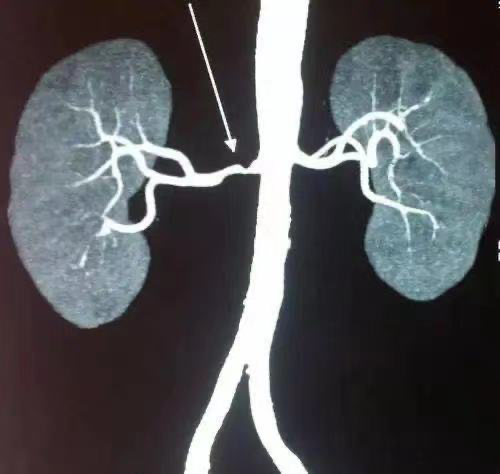

诊断肾动脉狭窄最简单、有效的方法就是经济且无创的肾动脉超声。在检查之前,尤其是肥胖患者,一定要空腹且应排尽粪便,并配合医生的呼吸指令。若超声检查仍难以辨清,则需遵医嘱做进一步检查(如CT或磁共振成像)以明确肾动脉的情况,虽然检查费用略高一些,但也一定要查。除了这些影像检查,还需进行血液生化检验及尿液检验以明确肾功能的状况。

多种影像学检查可确诊肾动脉狭窄